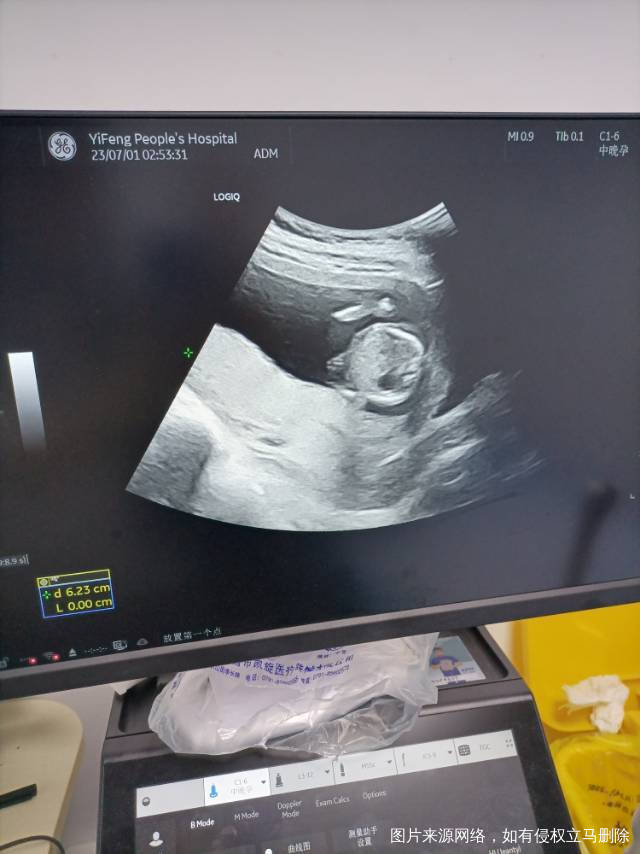

今天是怀孕16周去做了胎心监测还有做了一个B

正常的胎盘附着于子宫体部的前壁、后壁或侧壁,远离宫颈内口。妊娠28周后,胎盘仍附着于子宫下段,其下缘达到或覆盖宫颈内口,位置低于胎儿先露部,称为前置胎盘。你的情况,现在孕周还小,还不能确定是前置胎盘。遵医嘱用药吧!注意休息,观察是否有阴道流血,如果有阴道流血,及时去医院。